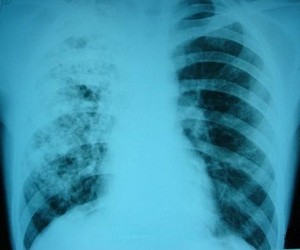

Министерство здравоохранения заявляет о снижении уровня заболеваемости туберкулезом. По данным ведомства, за последние 7 лет число заболевших в Украине уменьшилось на 20% и составляет менее 1% населения. Общественные организации не согласны с официальной статистикой. По их словам, в нашей стране не организован ежегодный профилактический осмотр граждан, из-за чего нет возможности назвать точное количество заболевших туберкулезом.

По данным Министерства здравоохранения, в 2012 году в стране насчитывалось 68,1 больного туберкулезом на 100 тыс. населения. Количество смертей от этого заболевания составляет 15,2 на 100 тыс. Почти такие же показатели Минздрав сообщал и в прошлом году: на 100 тыс. населения приходилось 67 случаев болезни, из них 15 — с летальным исходом. «За последние годы нам удалось преодолеть эпидемию туберкулеза. Мы наблюдаем сокращение заболеваемости, распространенности и смертности от этого заболевания»,— заявил заместитель министра здравоохранения Александр Толстанов. «Мы сейчас не говорим об эпидемии. По нормам Всемирной организации здравоохранения о ней можно говорить, когда болеют более 1% населения. У нас пока лишь высокий уровень заболеваемости туберкулезом, поскольку болеют менее 1%»,— поддержал коллегу главный пульмонолог Минздрава Юрий Фещенко.

Положительную статистику подтверждают и в Государственной службе по вопросам противодействия ВИЧ-инфекции/СПИДу и другим социально опасным заболеваниям. «Начиная с 2006 года наблюдается положительная тенденция по борьбе с туберкулезом. В 2012 году уровень заболеваемости на 20% ниже, чем в 2005 году. Под наблюдением врачей находятся 61,7 тыс. пациентов»,— отметил первый заместитель председателя госслужбы Евгений Ханюк.

Вместе с тем, по мнению главы правления общественной организации «Украинцы против туберкулеза» Виталия Руденко, говорить о преодолении эпидемии туберкулеза Украине пока рано: «Выводы Минздрава вызывают у меня улыбку. Какие могут быть успехи, если государственная программа по туберкулезу, рассчитанная до 2016 года, не финансируется в полном объеме, а мероприятия предыдущей программы также выполнялись на 40%? У нас нет обязательного ежегодного профилактического осмотра, поэтому мы не можем с точностью сказать, сколько у нас сейчас больных туберкулезом. Если обследовать всех бездомных, сельское население, трудовых мигрантов, беженцев, безработных, то официальные цифры можно будет увеличить минимум в два раза».